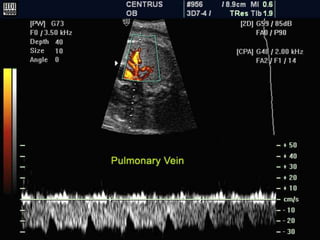

Normal Ductus venosus Blood Velocity

• The ductus has a usually high flow during the

entire cardiac cycle compared to the

neighboring veins.

• Starting the early gestation the velocity

increases to reach a plateau at 22 weeks.

• For the rest of the pregnancy the PSV ranges

between 40-85 cm/s

• The velocity pattern reflects the with a peak

during systole and another during diastole ,

and a nadir during active diastolic filling(atrial

contraction).

• Typically this nadir doesn’t reach zero or

below zero during the second half of

pregnancy.

• However below 15 weeks a nadir zero or

below zero is being recorded in normal

fetuses.